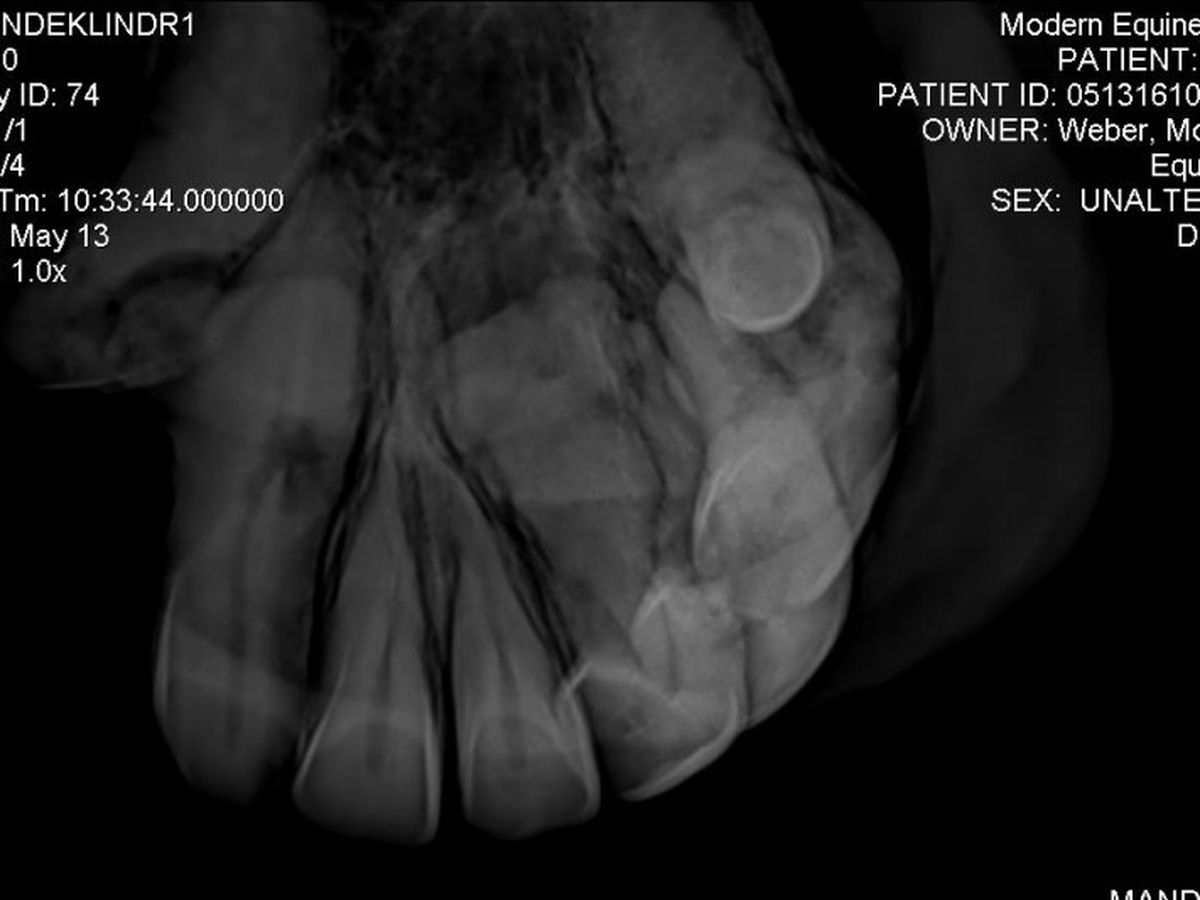

Those who know me well also have had the pleasure of meeting my life long best friend, Harli. He is a pure Spanish Arabian who just turned 26 on Friday the 13th. We have been by each others sides for 16 years - since I was 12! On his birthday Harli had X-rays done on his front teeth because the Vet suspected he had EOTRH *For more detailed info on the disease, see website : http://www.midwestequineservices.com/eotrh-syndrome/

Having done full blood panels and testing for other disorders and diseases to have them all come back negative, with X-ray images such as the one provided, it is clear now that this dental disease, which has gone undetected in Harli for what appears to be many years now, is the cause of his dramatic weight loss and inability to gain weight.

Unfortunately he has a very serious case of this dental disease newly identified in the equine world. Not much is known as to the cause nor the preventative treatment, but once a horse has it all that can be done is to remove the teeth entirely. Harli needs most if not all of his front teeth surgically removed at a surgical facility in Gilroy, CA so that his chronic pain can end.